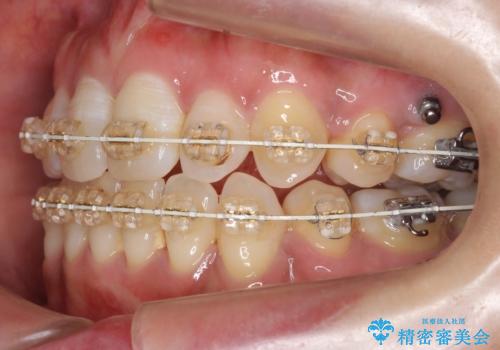

- 矯正装置

- 審美装置

- 2年5ヶ月

右上以外の3本を抜歯しきちんと並べました。

成人の矯正でしたので、矯正治療前にしっかり必要な歯周病治療を行い、状態が改善してから開始しました。